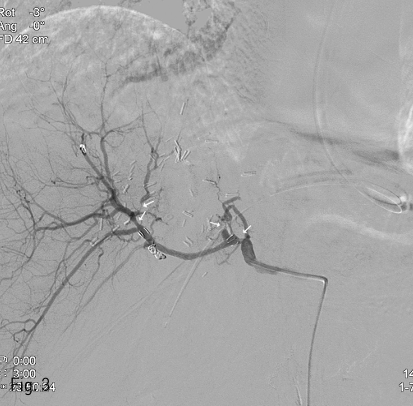

응급 복부 CT에서는 뚜렷한 활동성 출혈 병소는 찾을 수 없었으나, 응급 상부위장관 내시경에서 십이지장 구부에 약 3mm 크기의 박동성 종괴가 확인되었다 (Fig. 1).

Fig 1

Emergency upper GI endoscopy revealed a pulsatile vascular lesion (about 3mm in size) at the duodenal bulb.